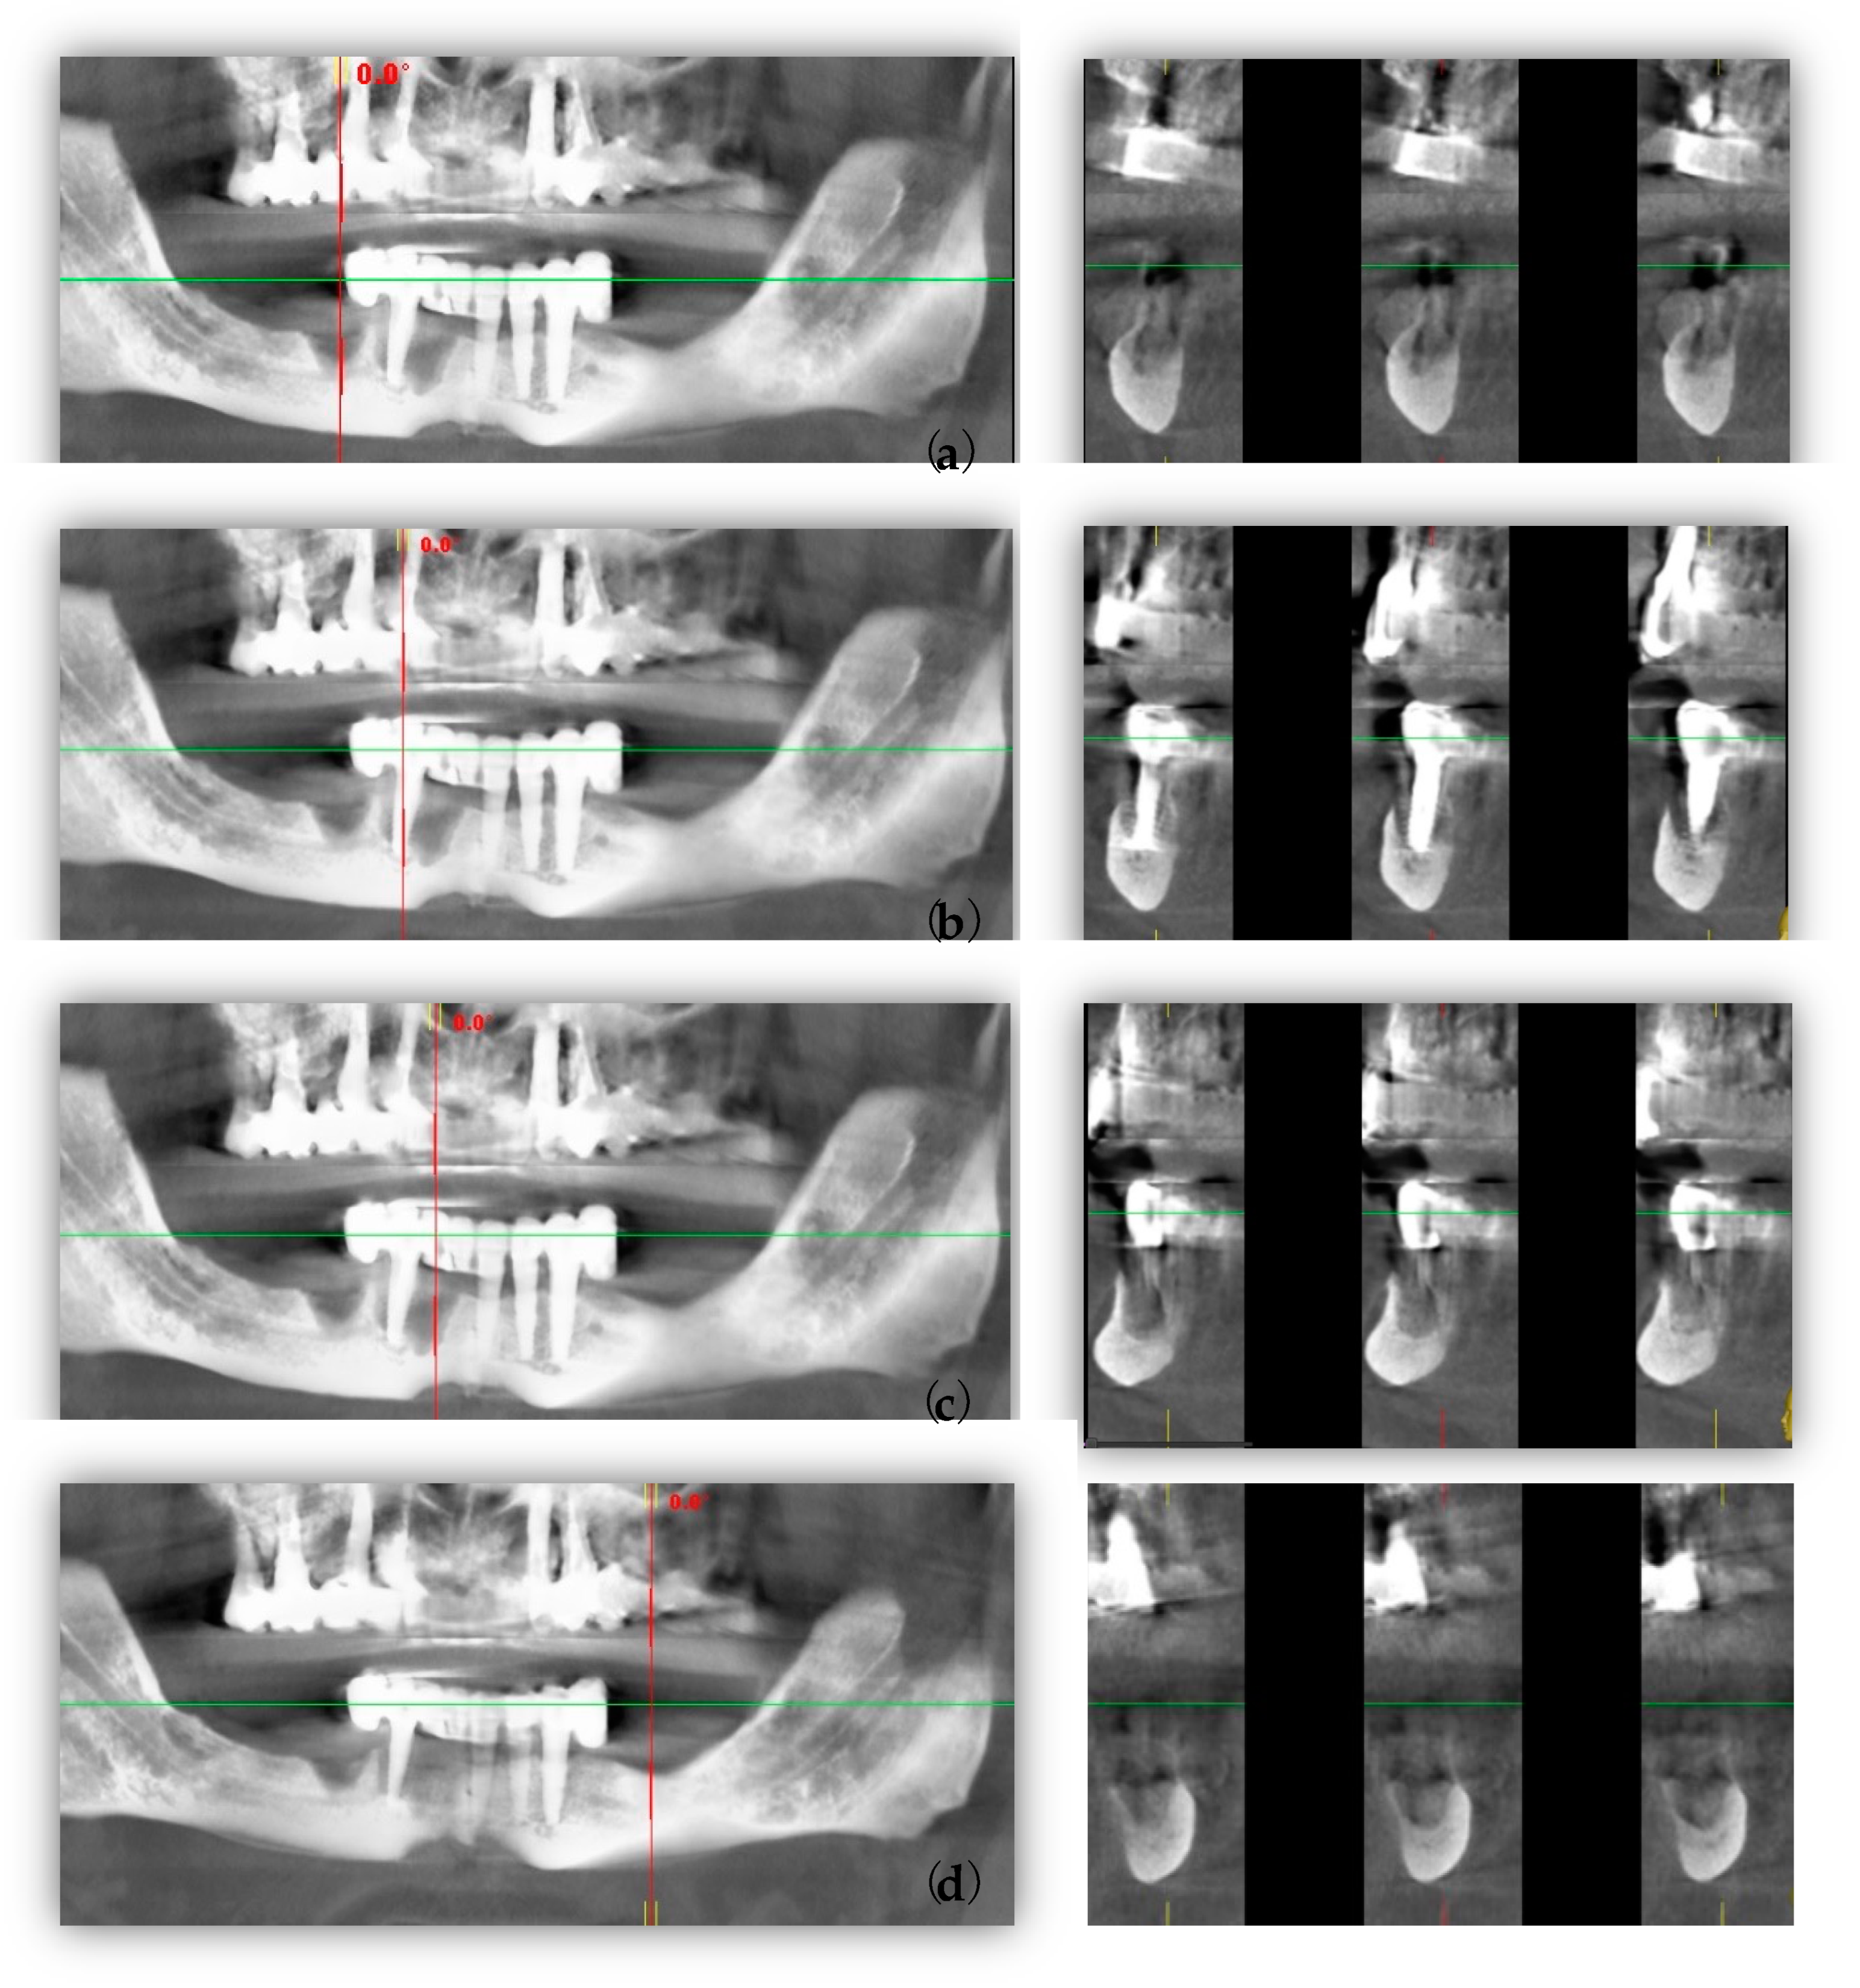

Cone beam computed tomography (CBCT) revealed that the three remaining implants in the anterior left mandible side had appropriate implantation and decent appeal (Figure 2a–d).

Figure 2.

Pre-surgical CBCT images: (a) panoramic (green line) and cross-sectional (red line) views of bone defect after implant failure; (b) panoramic (green line) and cross-sectional (red line) views of 4.3 implant; (c) panoramic (green line) and cross-sectional (red line) views of bone defect after implant failure; (d) panoramic (green line) and cross-sectional (red line) views of bone defect after implant failure.